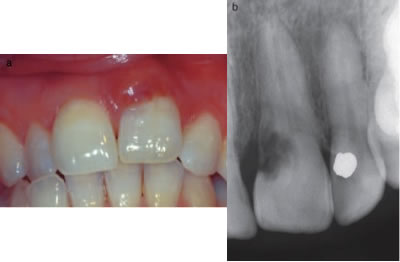

A major challenge with ECIR lesions is they are typically asymptomatic and difficult to discover unless they are at a class III or IV. If clinically detectable, a tooth may take on a pinkish hue near the gingival margin, due to the highly vascular inflammatory tissue that is replacing the tooth structure. There may be a cavitation that is detectible with an explorer. The tooth structure is usually hard, not sticky as is the case when detecting a carious lesion, however large lesions may also have secondary decay as a result of the defect creating a hygiene issue. Localized periodontal inflammation may also be observed for this reason as well. (Figures 5 and 6)

Figure 5- Small ECIR defect detectible at the gingival margin of #8. The pinkish hue of the inflammatory tissue is visible through the translucent enamel. Associated radiograph is included.

Figure 6- localized periodontal inflammation as a result of an ECIR lesion #9. Associated radiograph is included.